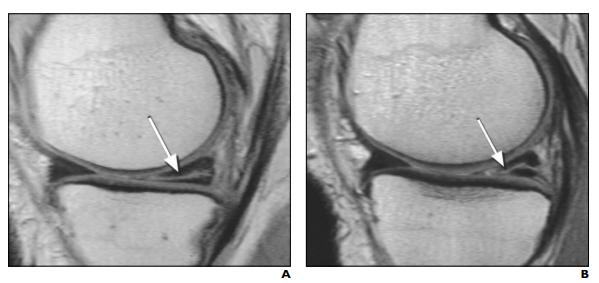

根据磁共振上,半月板的异常表现不同,我们将半月板损伤分为1-3级。其中:

1级损伤:是指半月板最轻微的病变,只是“垫子”里面出了一点点小问题,垫子外观看还是完全正常的,表面都很光滑没受损。

2级损伤:是指半月板中度的病变,损伤范围比1级要大,但是损伤都在内部,没有累及到半月板表面,没有通关节,半月板的表面依旧是光滑完整的。

3级损伤:是半月板较为严重的损伤,指半月板的撕裂样损伤,已经累及到表面,半月板表面不光滑了撕开了。

1级和2级的半月板损伤,都是首选保守治疗(休息、理疗、服药、关节内注射),不用手术;而3级半月板损伤,尤其是年轻人的急性损伤,一般都需要手术,而且需要尽快手术。